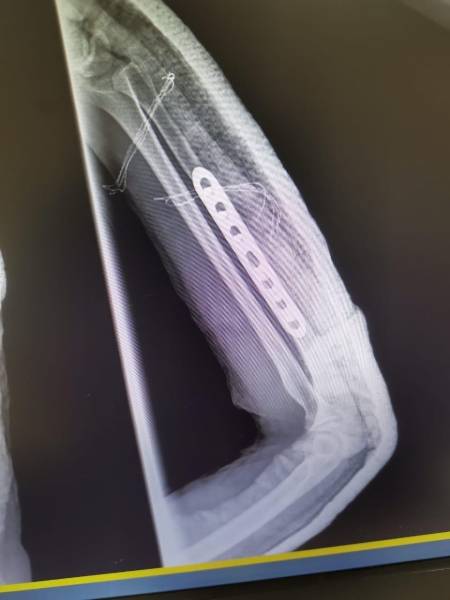

- إجراء عمليات جراحية معقدة و دقيقة في مجال العظام و المفاصل و الكسور و الإصابات ، رغم الضغط الكبير على المستشفى و أعداد المراجعين الكبيرة.

- تطبيق تقنيات جراحية حديثة و متقدمة، و ذلك في ظل التحديات التي يواجهها الفريق بسبب أعداد المرضى و المراجعين الكبيرة.